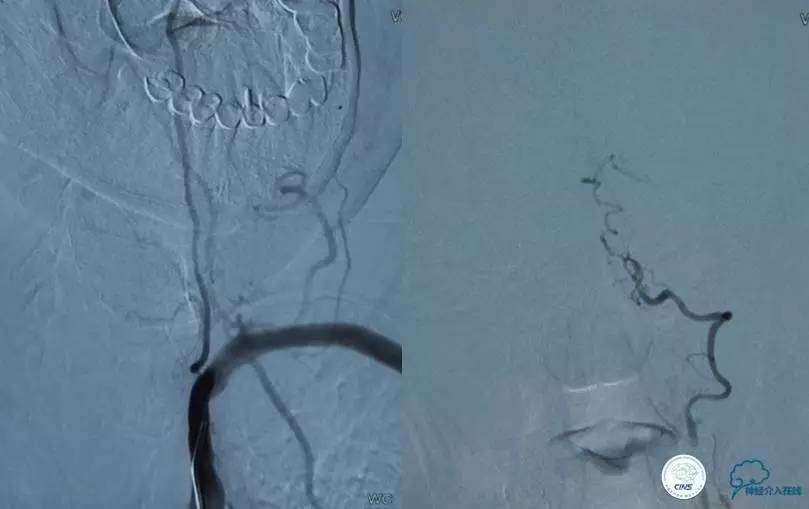

患者:侯XX,男性,64岁。因“持续性头晕8天”于2014-11-27入我院。

现病史:患者8天前无明显诱因出现头晕,旋转性,持续性,休息时可减轻,体位变化时加重,肢体活动正常,无恶心、呕吐、听力下降,无视物重影,无肢体抽搐。入院2天前当地脑血管造影示“右椎动脉狭窄”,给予药物治疗,具体不详,效果差,转来我院。饮食、大小便正常,体重无明显变化。

既往史:高血压、糖尿病病史20余年,胰岛素治疗,控制一般。无嗜烟酒史。10年前右胫骨骨折病史。

查体:老年男性,神志清、精神可。语言流利。双肺呼吸音清,心率60次/分,各瓣膜听诊区无杂音。两侧瞳孔等大等圆,对光可,各向运动无明显受限,上视、水平时可见眼球震颤。两侧鼻唇沟对称,伸舌居中。两侧肢体肌力5级。肌张力正常。无明显感觉减退。四肢腱反射对称。共济失调征(-)。双侧病理征(-),脑膜刺激征(-)。

▼影像学资料

入院后,患者症状稍有加重,出现走路不稳,查体发现两手指鼻不稳。行颅脑MRI检查。给予双抗血小板、调脂、改善脑循环、营养神经等药物治疗。立普妥20mg qn。实验室检查:LDL-C:3.31mmol/L。

▼颅脑CT灌注扫描

▼2014-12-08

▼Apollo 3.0*13mm